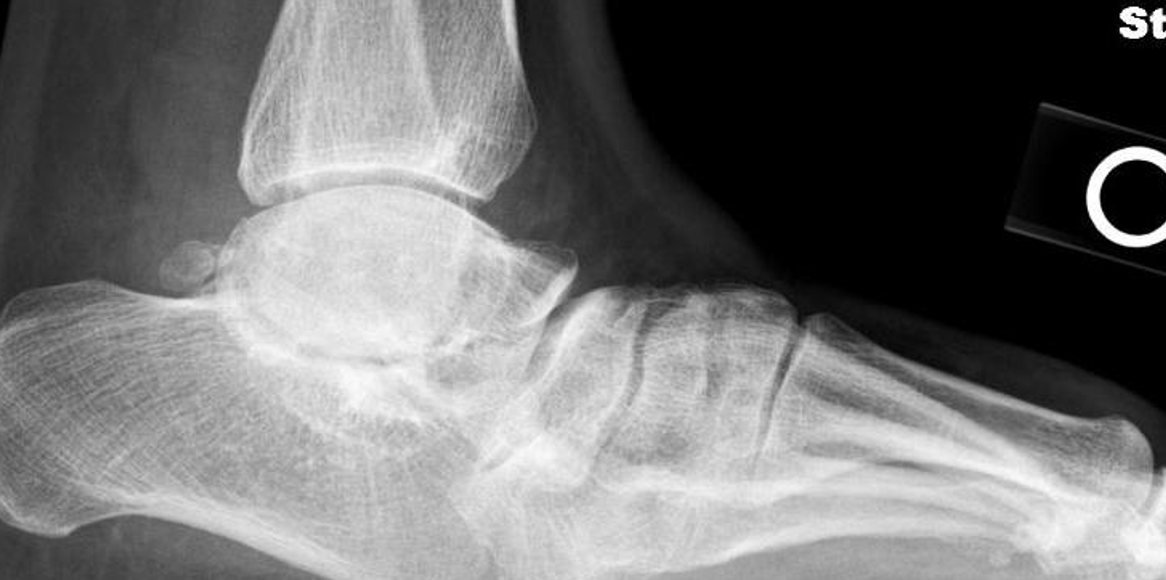

One of the most disturbing complications with any casting is the development of flat top talus. Overly aggressive attempts to dorsiflex the ankle often lead to met primus elevatus, but the flat top talus ruins the ankle joint during development. When I work with residents and students, I always stress the importance of avoiding dorsiflexion completely during the casting phase simply because I do not want to create a deformation of the talus. I reserve all of my sagittal plane correction for the Achilles lengthening and posterior capsule release. Unfortunately, I see more and more cases of flat top talus as a result of the Ponseti method. Khan and colleagues in 2021 reported a significant increase in their study and review of the literature, blaming it solely on overly aggressive casting and manipulation.16

So, to summarize, true congenital clubfeet have abnormal talar bodies, which lead to abnormal ankle and subtalar joints with short Achilles and tight posterior tibial tendons. Regardless of treatment, there is nothing anyone can do to make the talus a normal bone. Many of these cases can and will develop additional deformities. Only the Cincinnati release can address every issue associated with the deformity, but it is NOT a cure. The Ponseti procedure is a total compromise, also NOT a cure. The sooner everyone treats the Ponseti as a compromise, I believe we will be far happier with the outcomes. I remember discussing this with others treating pediatric orthopedic issues during the rise of the Ponseti in the early 2000s. We all agreed, undercorrecting the deformity will lead to more surgeries and residual deformities. Until we all face the reality that clubfeet are a genetic deformity and not just a positional deformity, we will never make them perfect. Thus, athletes and the military will put any and all clubfeet patients to the test. There is no doubt that exceptions exist, but in time, at least based on our limited review of over 1000 clubfeet and 250 cases we saw in the military, no one is immune to complications, arthritis, and ultimately disability.

Here is a typical case presentation. A 21-year-old Marine at Ft. Leonard Wood for training underwent a Cincinnati release at one year old and had stellar follow-up. Her surgeon even wrote her medical waiver for entrance into the Marines. She ran track in high school. She finished boot camp and completed all of her Marine training, but now has chronic pain. She no longer can run. She hasn’t passed her physical training in over a year. She developed talonavicular DJD. By all accounts, her overall clubfoot should be rated an A+; no residual deformity, normal talocalcaneal angles on AP and lateral views, no equinus, no residual varus, only slight met primus elevatus, but no signs of a flattop talus. Clinically, she lacks subtalar range of motion, which I commonly find post-clubfoot release of any kind. So many in the military do very well for a while, but the demands of the military eventually catch up to them. We all root for clubfeet to make it, but the odds are stacked against them.